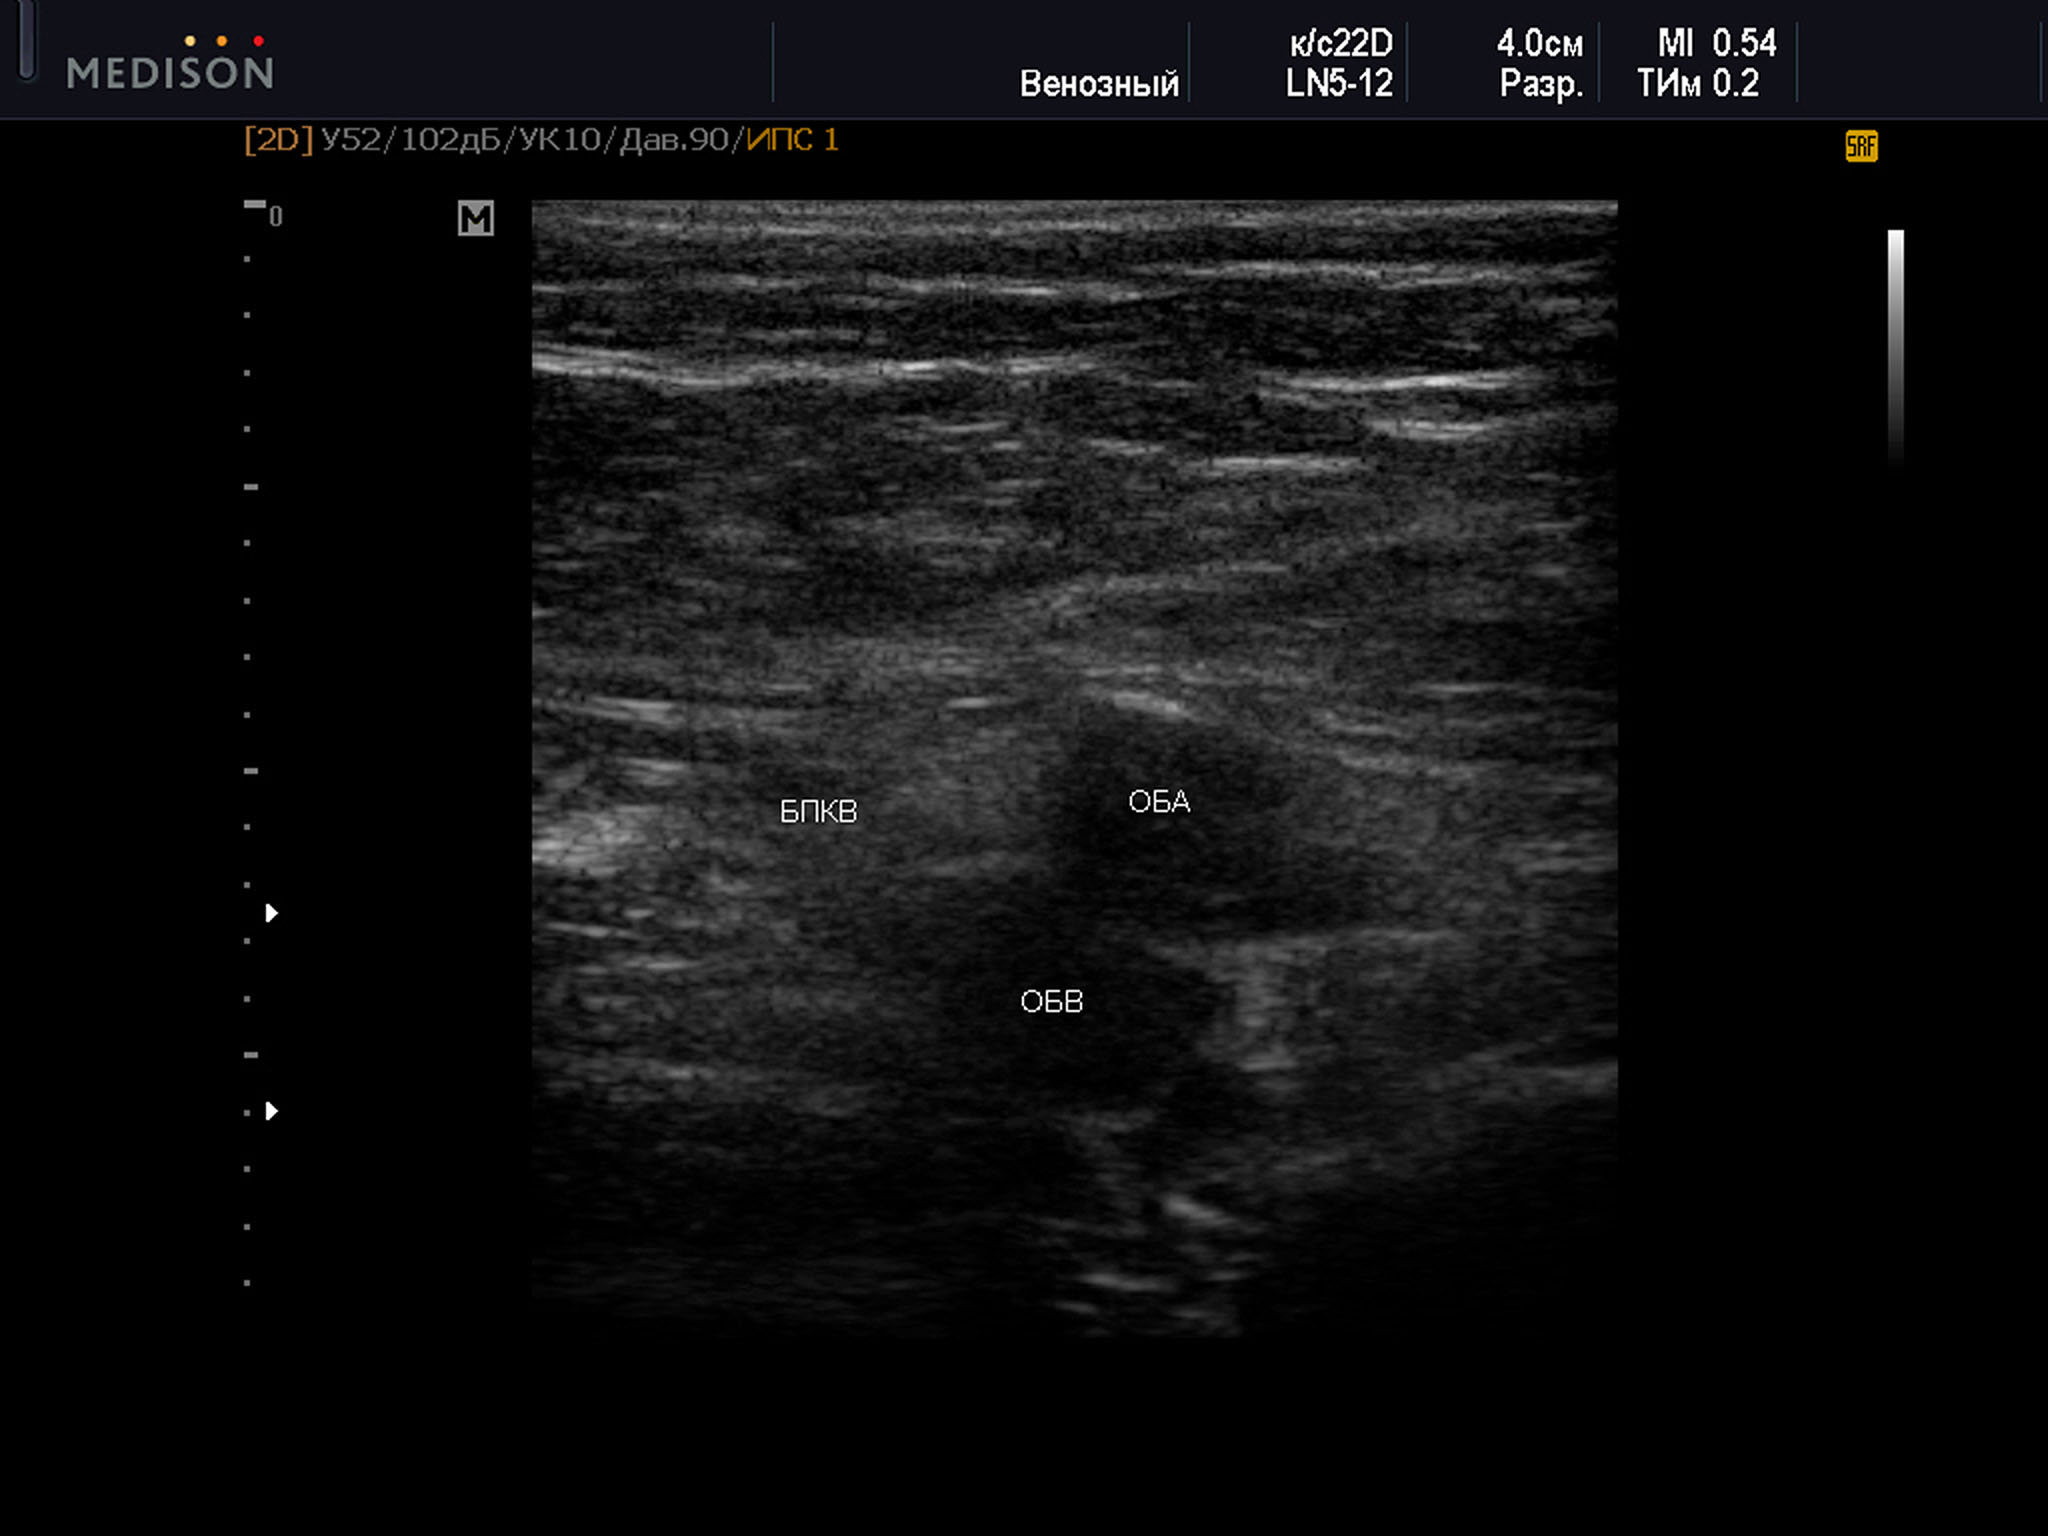

Пример диагностического ультразвукового изображения на уровне верхней трети бедра, поперечное сечение общей бедренной вены и общей бедренной артерии, Тип 2 взаимного положения сосудов

SonoAce R7, линейный датчик, мужчина, 55 лет.

ОБА – общая бедренная артерия; ОБВ – общая бедренная вена; БПКВ – большая подкожная вена бедра

2 тип оказался самым распространенным, составляя 33% от общего числа наблюдений. При этом в 36% был диагностирован справа, и в 29,8% — слева. Среди женщин данный тип встречался в 33,8% наблюдений. Справа данный вариант положения сосудов был выявлен в 35,8%, а слева в 31,7%. В группе мужчин представленный вариант расположения сосудов определялся в 31,8% всех наблюдений. Значительно чаще был выявлен справа — 36,2%, а слева в 26,8%. Возраст всех участников с данным типом положения сосудов был от 28 до 79 лет — 54,7±13,3 года, среди женщин возраст был от 28 до 79 лет — 52,9 ± 13,8 лет, возраст мужчин был от 28 до 78 лет — 57,0 ± 11,8 лет.